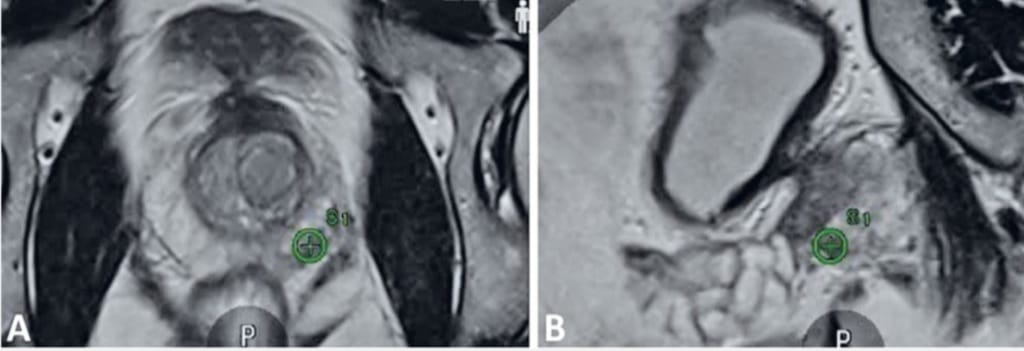

A szatmári kórház közlése szerint, az MRI-fúziós eljárás a multiparaméteres MRI (mpMRI) felvételeit ötvözi a transzrektális ultrahangvezetéssel. Ennek köszönhetően az orvos a prosztata már előzetesen azonosított, gyanús területeiből tud szövetmintát venni, jelentősen növelve a diagnózis pontosságát a hagyományos, „vakon” végzett biopsziákhoz képest.

Az eljárás alapja, hogy az MRI-felvételeket valós idejű ultrahangképekre vetítik rá. A speciális szoftver a két adatbázist egyesíti, és részletes, háromdimenziós térképet hoz létre a prosztatáról. Ez lehetővé teszi a magas kockázatú, MRI által PIRADS-gyanúsként jelölt elváltozások célzott mintavételét.

A pontos lokalizáció kulcsfontosságú a személyre szabott terápiás terv kialakításában – legyen szó aktív megfigyelésről, célzott kezelésről vagy radikális beavatkozásról. A módszer ideális egyensúlyt teremt pontosság, biztonság és betegkomfort között, és megerősíti a korszerű képalkotás szerepét a prosztatarák korai felismerésében.